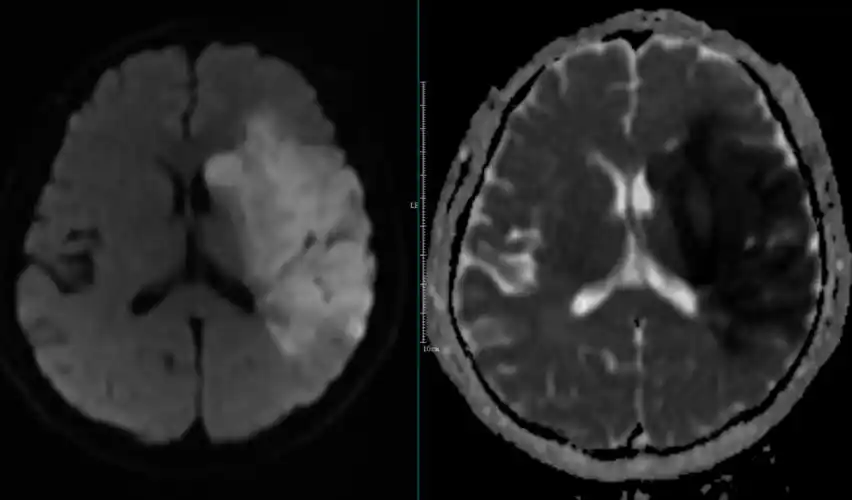

67超急性期大面积脑梗死ct平扫表现